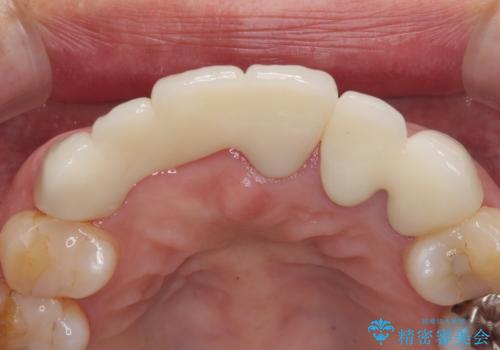

抜歯および根管治療を実施した後にオールセラミッククラウンにて補綴することとしました。

歯肉ラインの改善には歯周外科処置が必要でしたが、大きく笑っても歯肉ラインが唇に隠れるとのことで、外見の改善はせず、清掃性の大会ブリッジを装着いたしました。